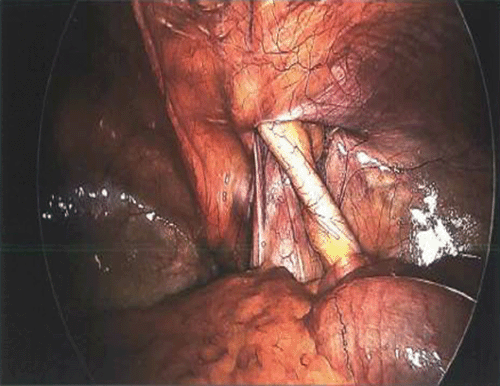

We describe the case of an 84-year-old female presenting with a right Amyand’s hernia containing a perforated appendix and a large associated abdominal wall abscess. Her medical history includes hypertension, dementia, and no prior surgical interventions. She presented to the emergency department with a one-week course of progressive right lower quadrant pain, nausea, and chills. During the initial evaluation, she was found to be febrile. Her physical exam noted right lower quadrant tenderness with overlying skin erythema and fluctuance to palpation. A computed tomography (CT) of the abdomen and pelvis showed an incarcerated, perforated appendix coursing into the right inguinal canal with an adjacent 6.9 × 4.5 × 7 cm abdominal wall abscess. She was admitted to the hospital for intravenous antibiotic treatment and percutaneous drainage of the abscess by interventional radiology. The abscess culture grew Escherichia coli and Streptococcus anginosus. On hospital day 10, she was discharged to a nursing facility for drain care, where an oral course of amoxicillin-clavulanate for 14 days was completed. Approximately one month later, the patient returned to the operating room for an interval laparoscopic appendectomy. Upon exploration of the abdomen, the appendix was found to be incarcerated within the right inguinal hernia. Once successfully reduced, a standard laparoscopic appendectomy was completed. No fluid collections were evidenced in the abdomen or abdominal wall. A large right inguinal defect was visualized, and the decision to pursue a definitive hernia repair at a later stage was made, given her high risk for mesh infection. Her postoperative course was uneventful. During her postoperative follow-up, her son and heath care proxy decided not to pursue hernioplasty, given her recent functional decline and high morbidity risk.

Figure 3. Intraoperative Image of Incarcerated Appendix Within Right Inguinal Hernia. Published With Permission